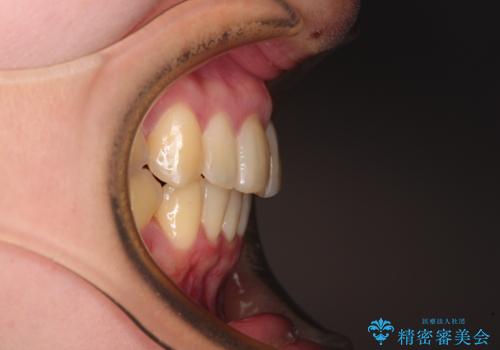

- 前歯の著しい叢生と前突感を気にして来院された患者様です。

叢生が強いため、事前に前歯をワイヤー矯正で速やかに叢生を解消し、その後はインビザラインにて矯正治療を行うこととしました。

ワイヤー矯正を併用したことで前歯の叢生を速やかに解消することができました。

一方口元の突出感を改善するために時間がかかり、2年超を要しましたが、満足のいく仕上がりとなりました。